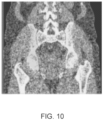

• a second machine learning module also referred to as a base Single Segmentation Machine 1208 (SingleSegMachine (base) in FIG. 12 ) performs a high-resolution segmentation of a CT image to identify a prostate volume corresponding to a prostate of the subject, along with additional tissue volumes corresponding to specific tissue regions, such as left and right gluteal muscles, a rectum, a bladder, a sacrum and coccyx, and left and right hip bones.

• the CT image is preprocessed to prepare it for segmentation by the second machine learning module.

• the CT image may also be cropped using the crop endpoints that identify the initial VOI (bounding box) and are output by the Localization Machine 1204, to produce a reduced, fixed size preprocessed CT image input for providing as input to a trained neural network (a trained CNN) associated with and implemented in Single Segmentation Machine 1208.

• the Single Segmentation Machine implements a trained CNN, referred to as a Segmentation CNN, that receives as input the preprocessed CT image.

• the second raw prediction map output by the Segmentation CNN comprises a channel corresponding to a prostate of the subject.

• the second raw prediction map may include other channels, corresponding to various additional tissue regions, such as a left gluteal muscle, a right gluteal muscle, a rectum, a urinary bladder, a sacrum and coccyx, a left hip bone, and a right hip bone.